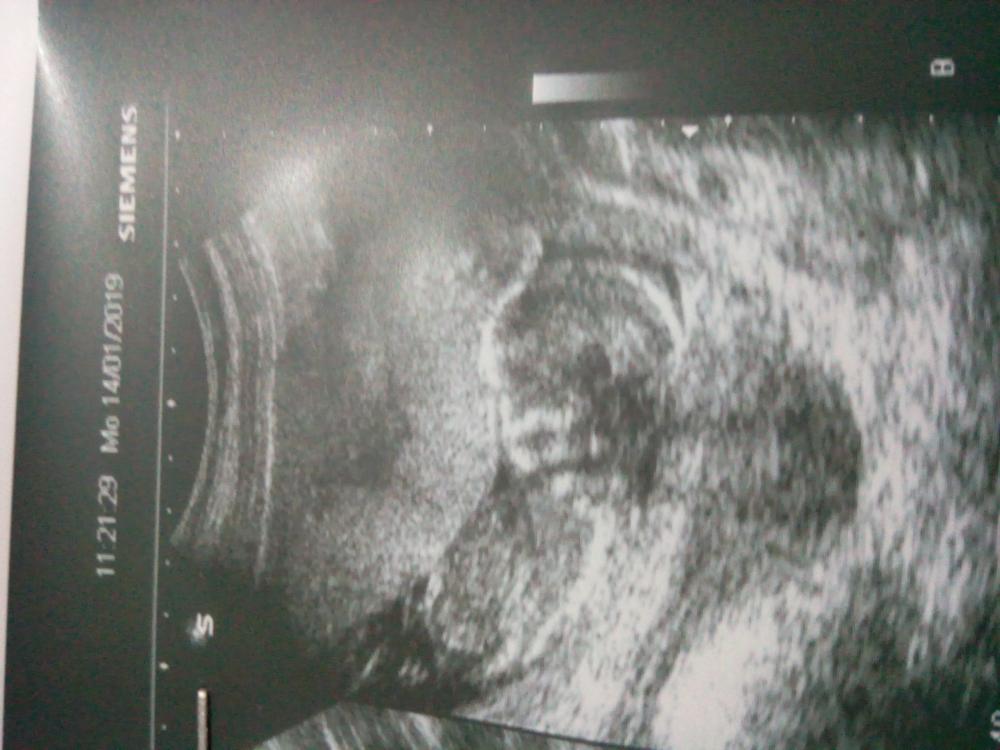

الحمل والإنجاب

اعرفي اعراض الحمل، متابعة شهور الحمل، تمارين الحمل، اعراض الولادة ، اصول الرضاعة الطبيعية